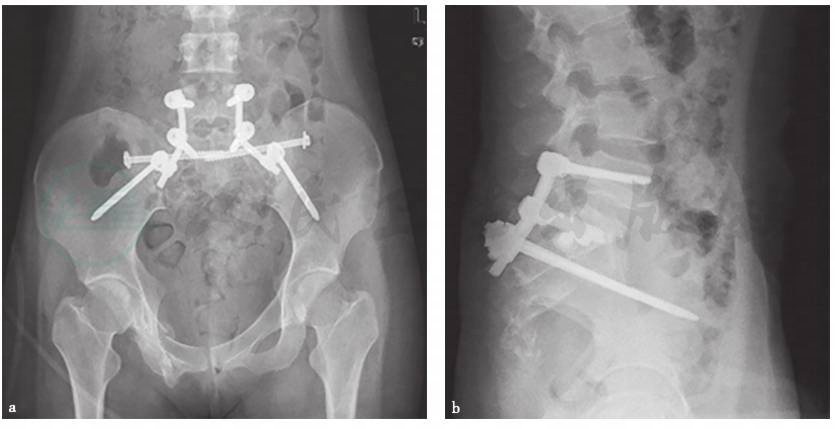

在完成陈旧性骨盆骨折的复位后,内固定物的选择相对于复杂的松解手术,其决策往往简单,不论是传统重建接骨板和螺钉,又或者是骶髂空心螺钉,大多取决于骨盆环损伤初始治疗时使用的内固定物。由于需要强大的力量维持复位,且陈旧性骨盆骨折患者的骨量往往较差,大多需要额外的固定策略,包括更大的内固定物、更多的固定点,甚至增加后方骶髂螺钉固定。近年来,髂腰三角固定(图1)的方案被广大医师所接受。有报道显示,其力学稳定性甚至远强于传统重建接骨板和螺钉,因此,对于手术无法松解或者骨折移位尚可接受的患者来说,髂腰三角固定配合植骨不失为一种可尝试的新方案。

图1髂腰三角固定

a.髂腰固定-骨盆入口位X线片;b.腰椎侧位X线片。